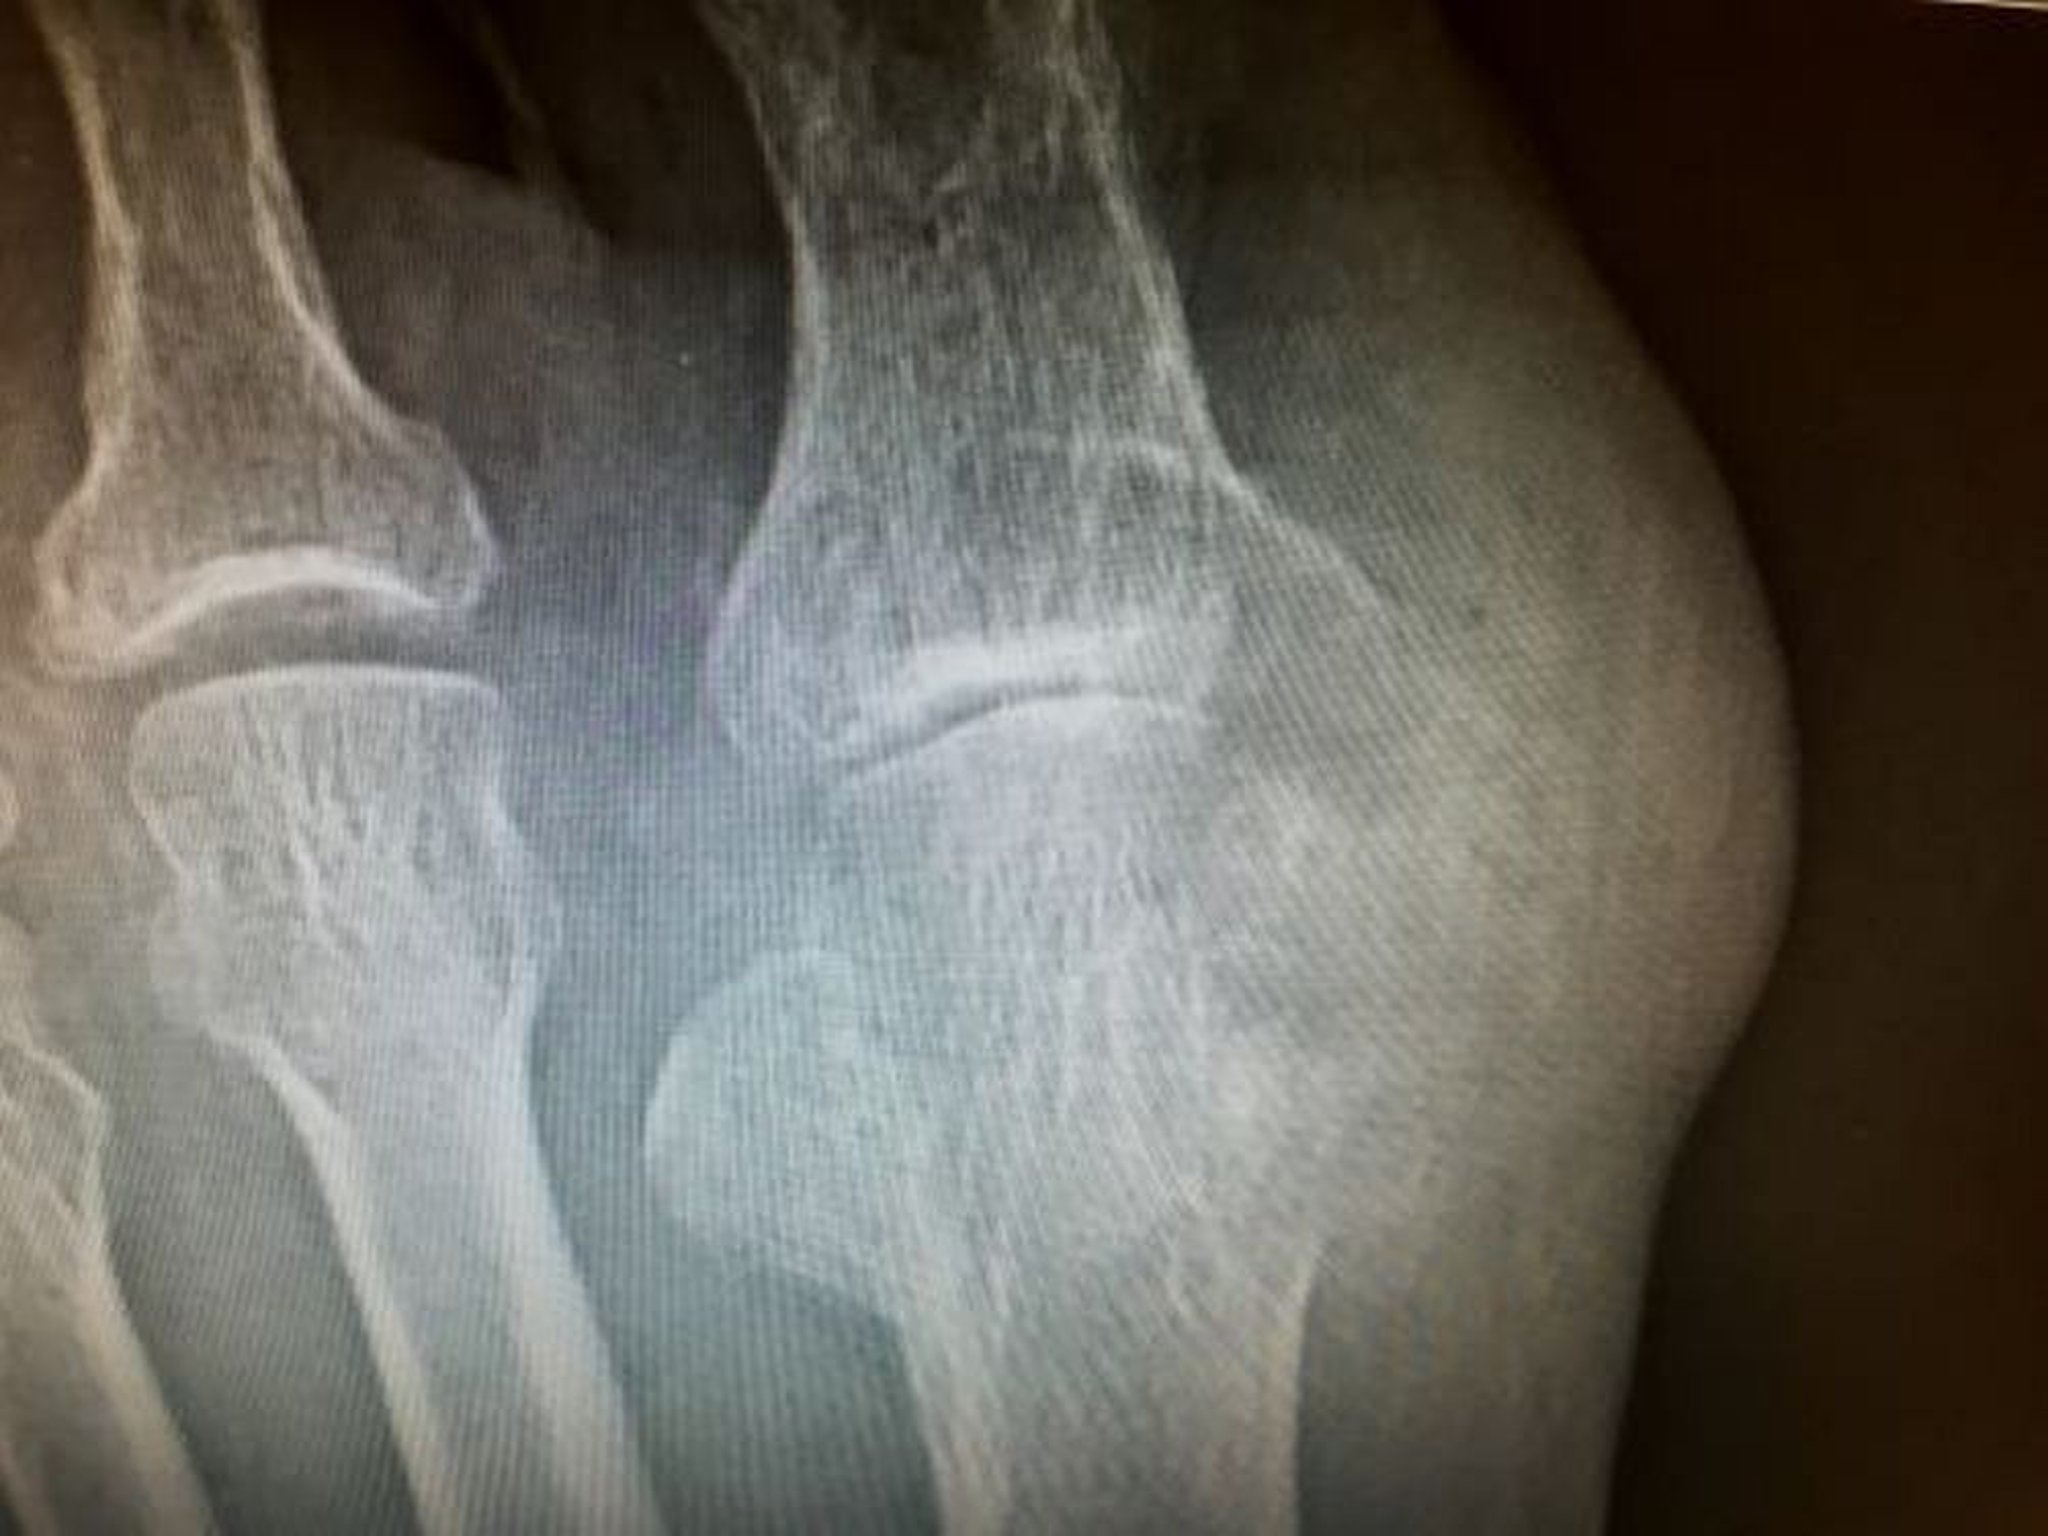

Tophus avec érosion

Cette photo montre de grandes érosions causées par des tophi impliquant la phalange distale métatarsienne et proximale du gros orteil.

Image courtoisie de N. Lawrence Edwards, MD.